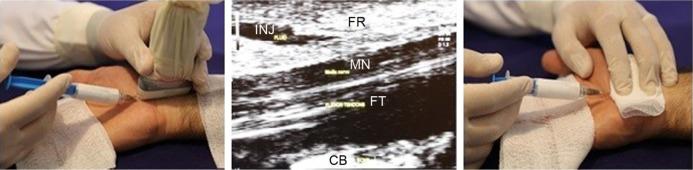

METHODS

We conducted a prospective, triple-blind, randomized, controlled trial in elderly patients with CTS. Patients were allocated to one of three groups by simplified randomization. Groups I-III received 80 mg triamcinolone (2 mL) and 1 mL of 2% lidocaine; 40 mg triamcinolone (1 mL), 1 mL of 2% lidocaine, and 1 mL normal saline; and 1 mL of 2% lidocaine and 2 mL normal saline, respectively to make up to 3 mL volume. A wrist splint was then applied for support. Outcome measures included the visual analog scale (VAS) and the Boston Carpal Tunnel Questionnaire, and median motor and sensory nerve conduction and its sonographic inlet cross-sectional area were used as objective measures. All data were recorded at baseline and 2, 12, and 24 weeks after injection. The investigators, patients, and statistician were blinded to the treatment assignment.

腕管综合征(CTS)在老年人群中较为常见,部分原因是易患合并症的存在增加以及生理变化。我们旨在比较超声引导下水分离法治疗老年 CTS 患者不同剂量类固醇的疗效。

方法

我们对老年 CTS 患者进行了一项前瞻性、三盲、随机、对照试验。患者通过简化随机化分配到三组之一。组 I-III 分别接受 80mg 曲安奈德(2mL)和 1mL2%利多卡因、40mg 曲安奈德(1mL)、1mL2%利多卡因和 1mL 生理盐水,以及 1mL 生理盐水和 2mL 生理盐水,总容量为 3mL。然后应用腕夹板进行支撑。主要观察指标包括视觉模拟评分(VAS)和波士顿腕管问卷,以及正中神经和尺神经运动和感觉神经传导的中位数及其超声入口横截面积作为客观指标。所有数据均在基线和注射后 2、12 和 24 周记录。研究者、患者和统计学家对治疗分配均不知情。